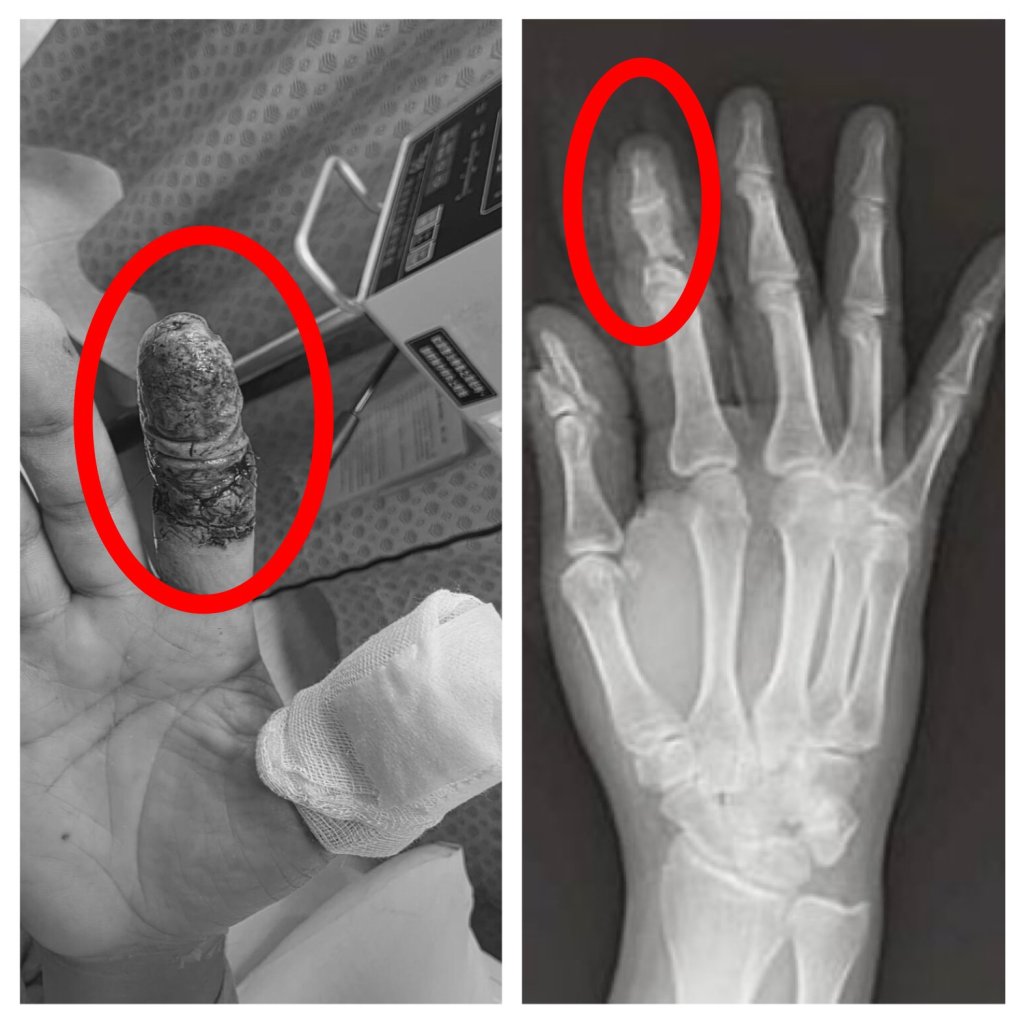

豐原一名45歲林姓男子日前操作大型無人機時發生意外,高速旋轉的螺旋槳瞬間擊中右手,食指幾乎完全斷離,僅剩少量皮膚相連,傷勢嚴重,緊急送往衛生福利部豐原醫院救治,經外科醫師陳明澤評估屬重大手指創傷,若血流未恢復恐須截指,立即進行清創與重建手術,透過顯微技術接合受損血管與組織,成功建立循環,為後續組織存活爭取關鍵時間。患者住院期間長達一個月,最終順利出院,成功保住手指外觀與功能。

豐原醫院外科醫師陳明澤指出,手指血管直徑僅約1-2毫米,顯微重接只是第一步,真正挑戰在於術後微血管血流的關鍵觀察期。陳醫師進一步表示,再接手指的血流極度脆弱,任何血栓都可能讓前功盡棄,因此團隊術後並未僅止於觀察,而是每日主動進行局部抗凝處置的特殊浸泡照護,使用的「Heparin」抗凝血藥物,採局部浸泡,輔助維持血管暢通、減少血栓形成風險,此療法屬於較細緻的術後血流管理策略,醫護人員需密集監測顏色、溫度與出血反應,是術後照護能力的重要延伸。

陳明澤醫師提到,患者住院期間長達一個月,初期因傷勢嚴重、復原緩慢,一度情緒低落甚至萌生放棄治療與轉院念頭,但在醫療團隊持續關懷與專業照護下逐步配合治療,隨著每日血流管理、一個月的高壓氧積極治療,手指循環逐步穩定、組織存活情況日益改善,讓患者逐漸重拾信心,最終順利出院,成功保住手指外觀與功能。